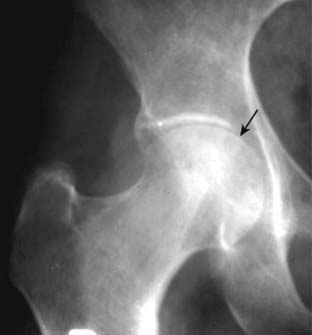

Figure 23-14 Rheumatoid arthritis of the hip.

The larger joints (hips and knees) usually show no erosions, but there may be marked uniform narrowing of the joint space with little or no subchondral sclerosis (solid black arrow). If this were primary osteoarthritis, you would expect far more subchondral sclerosis and osteophyte production for this degree of joint space narrowing.